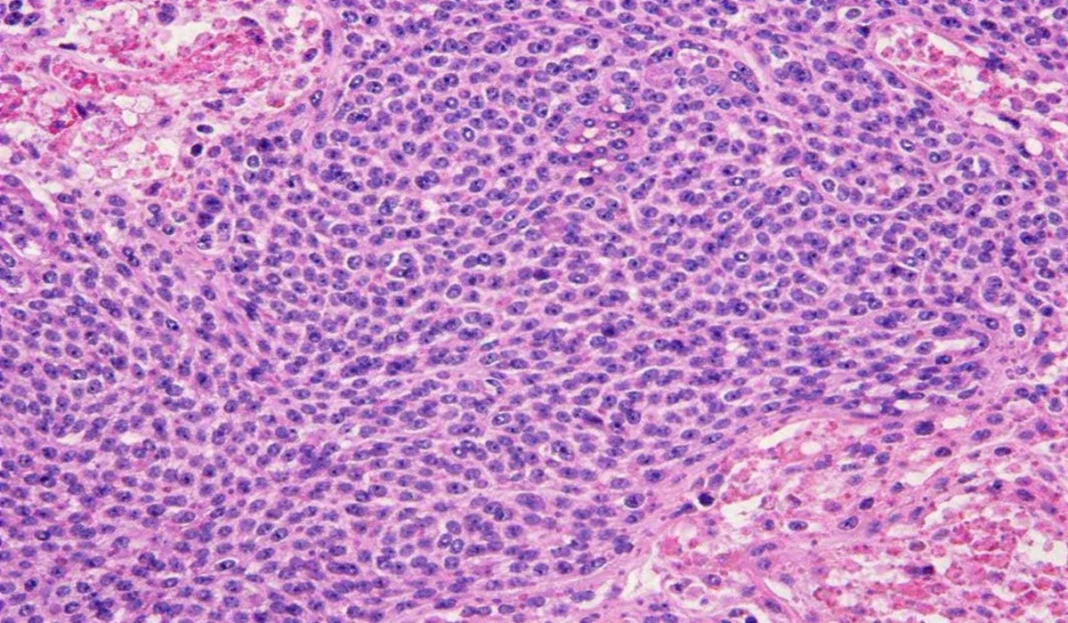

- Biopsy : Taking a sample of tissue from the tumor for microscopic examination. The biopsy may be performed with a fine needle (needle biopsy) or by surgery (surgical biopsy).

- Histologic Confirmation : Biopsy specimens are examined by a pathologist to identify microscopic features of Ewing sarcoma. This includes the presence of round tumor cells and identification of the characteristic chromosomal translocation (t(11;22)(q24;q12)) by techniques such as PCR (polymerase chain reaction).